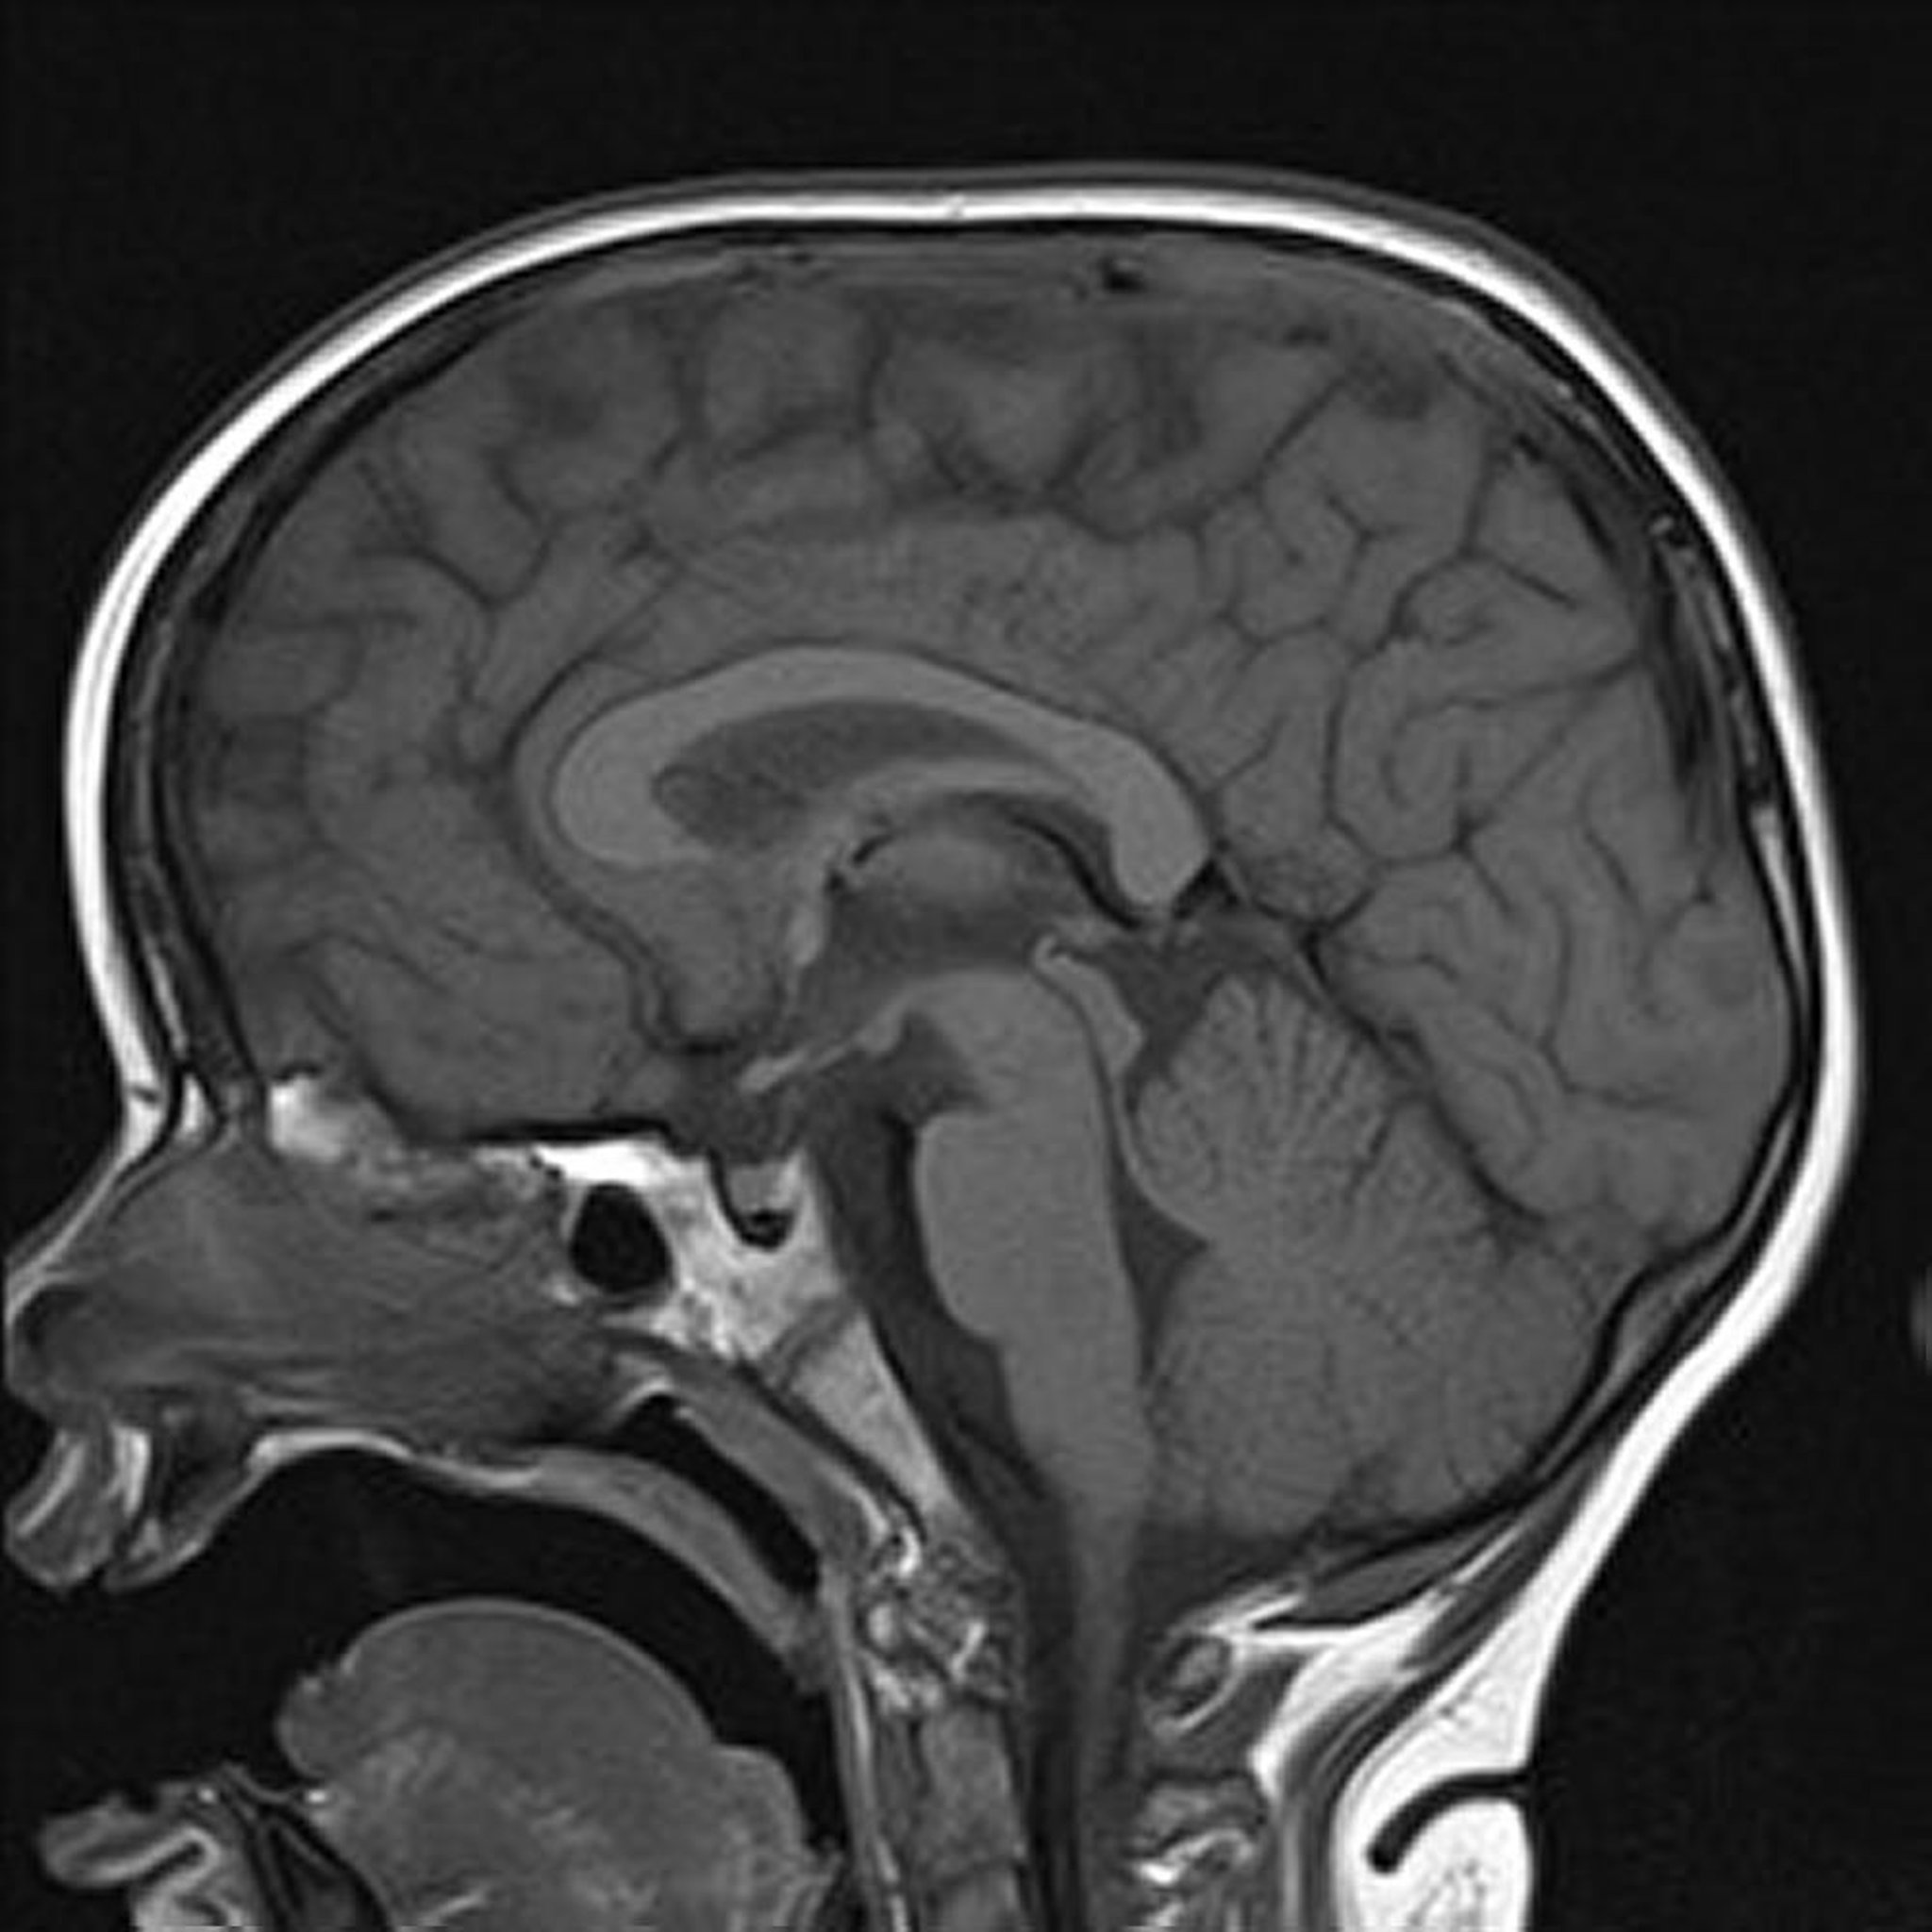

RM ponderada en T1

La imagen sagital ponderada en T1 del cerebro muestra estructuras normales de la línea media.

Image courtesy of Hakan Ilaslan, MD.